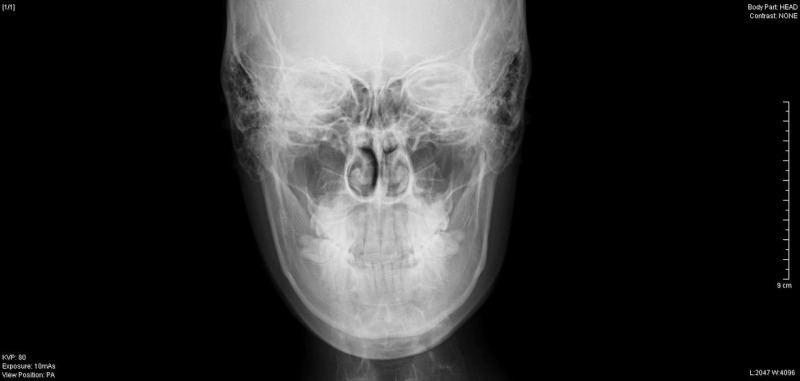

頭部レントゲン写真の側面写真で下顎骨の中央部より切り始め、